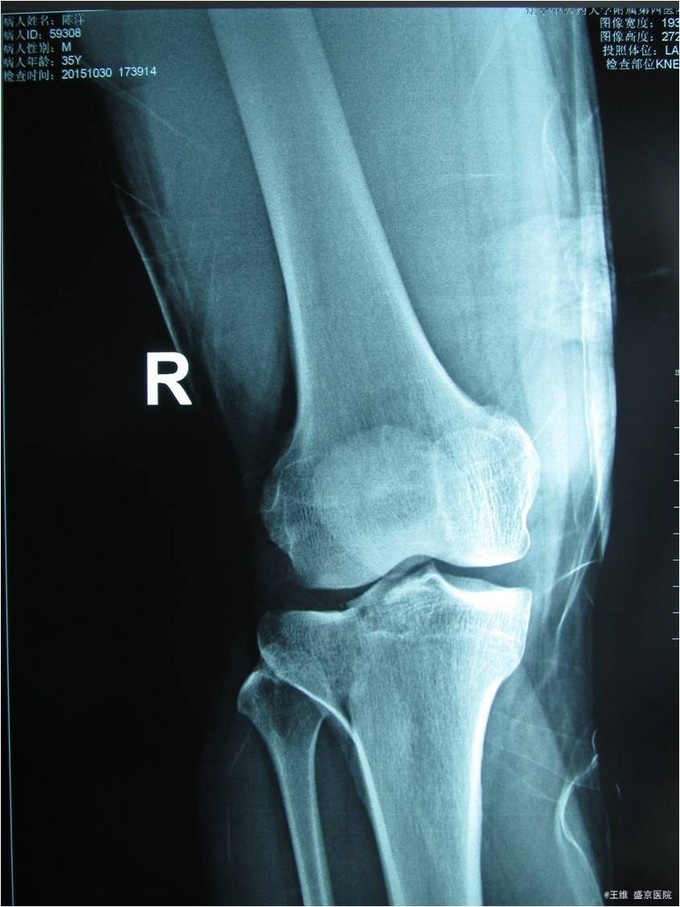

主诉:车祸致右膝部疼痛肿胀活动障碍5小时 现病史:患者及家属代述患者于2015年10月30日下午5点时在走路时被汽车撞伤发生车祸,导致右膝部疼痛肿胀活动障碍,当时无昏迷,送至沈阳中医4院,行DR及影像学检查示:右胫骨平台骨折,右12肋骨骨折。家属为行进一步治疗来我院就诊。经门诊检查后收入我科。患者病来,意识清醒,无头痛头晕,无咳嗽咳痰,无心慌气短,饮食正常,小便正常,大便未排,体重无变化。

专科查体:右小腿近端肿胀明显,无明显开放性创口,痛阳性,叩击痛阳性,可触及骨擦音骨擦感,压痛阳性,,右下肢感觉未见明显异常,右足趾感觉运动未见明显异常,双侧足背动脉搏动良好,末梢血运良好